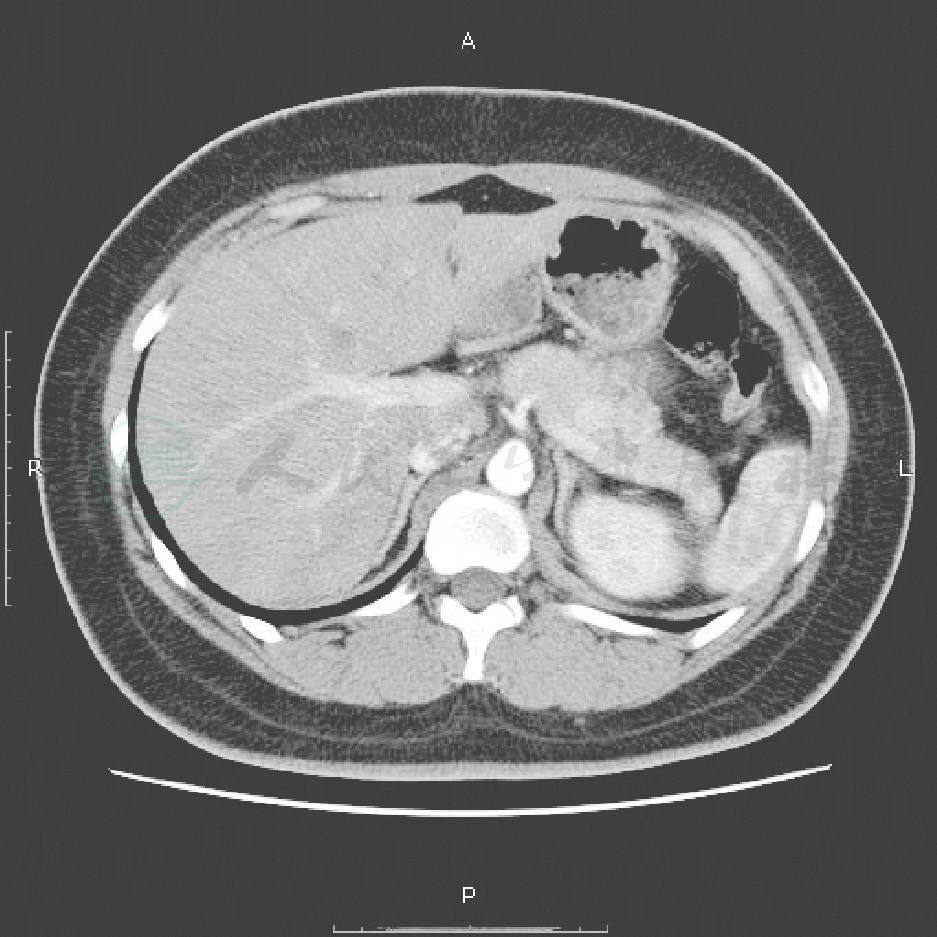

胰腺体部见一实性团块,约1.5cm×1.2cm的低回声,内部回声不均匀,边界清;诊断:胰腺体部低回声病变,胰岛细胞瘤可能性大(图1)。超声、腹部CT平扫+增强示:胰腺体部结节影(图2)。双侧肾上腺CT:未见异常。甲状腺、甲状旁腺超声:未见异常。垂体MRI平扫+增强:未见异常。患者胰岛素抗体阴性,不支持自身免疫性低血糖。甲状腺、甲状旁腺超声,垂体MRI,双侧肾上腺CT均未见异常,排除了多发性内分泌腺瘤。

图2 CT示胰体部高密度团块